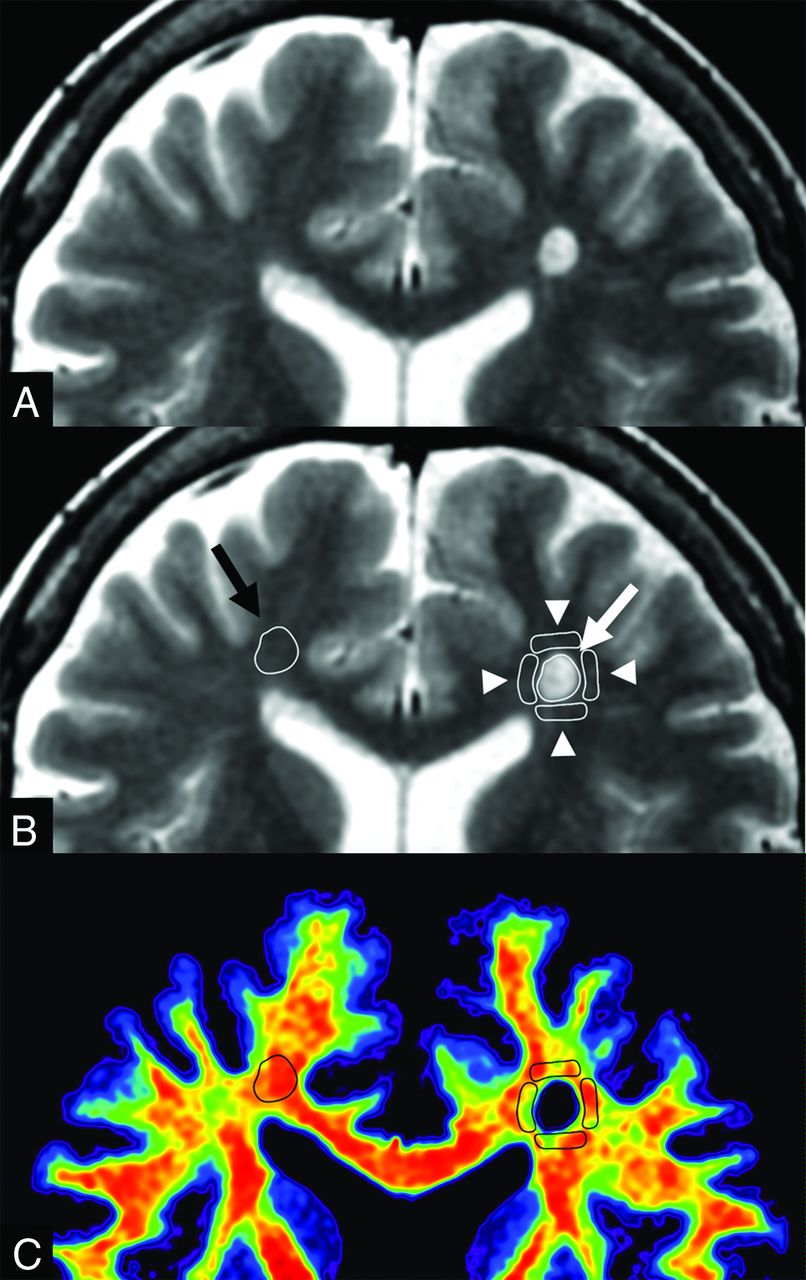

An example of ROI analysis in a patient with MS. The upper 2 images show the same synthetic T2WI without (A) and with (B) the placement of ROIs. A ROI (white arrow) was drawn on a plaque, and 4 ROIs (arrowheads) were placed on periplaque white matter to encircle the plaque. The ROI of the plaque was copied and pasted onto the contralateral normal-appearing white matter (black arrow). These ROIs were then copied and pasted onto maps of myelin volume fraction, axon volume fraction, and g-ratio. A map of the corresponding myelin volume fraction (C) is shown as an example.